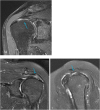

The rotator cuff is a group of four muscles and tendons surrounding the shoulder joint providing it strength and stability. The rotator cuff consists of the subscapularis, supraspinatus, infraspinatus and teres minor. Many shoulder complaints are caused by rotator cuff pathology such as impingement syndrome, tendon tears and other diseases e.g. calcific tendonitis. Diagnosis starts with clinical history and physical examination, after which imaging is often used to help confirm clinical findings depending on the differential diagnosis. The aim of the article is to review the frequently used imaging modalities to assess the rotator cuff and cuff-related disease, specifically focusing on radiography, ultrasonography and magnetic resonance imaging. This article will outline the advantages and disadvantages for each modality and illustrate typical radiological findings of common rotator cuff pathologies.